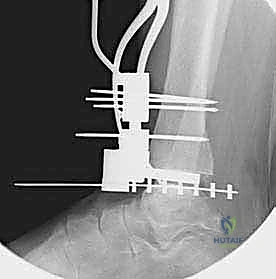

تعتمد دقة الجراحة على المحاذاة الصحيحة. يتم استخدام أجهزة توجيه متطورة (Jigs) تثبت على عظمة الساق باستخدام دبابيس معدنية. يتم التحقق من صحة الزوايا والمحاور باستخدام جهاز الأشعة السينية المباشر داخل غرفة العمليات (C-arm Fluoroscopy). يضمن الدكتور هطيف أن يكون القطع موازياً للأرض تماماً عند وقوف المريض.

5. القطع العظمي الظنبوبي (Tibial Bone Cut)

باستخدام منشار جراحي دقيق التذبذب، يتم إزالة شريحة رقيقة جداً (بضعة مليمترات) من السطح السفلي التالف لعظمة الظنبوب. يتم القطع بحذر شديد لتجنب إصابة الأوتار الخلفية أو الأوعية الدموية.

6. القطع العظمي الكاحلي (Talar Bone Cut)

بشكل مشابه، يتم توجيه دليل القطع نحو عظمة الكاحل (Talus) وإزالة السطح الغضروفي التالف وت